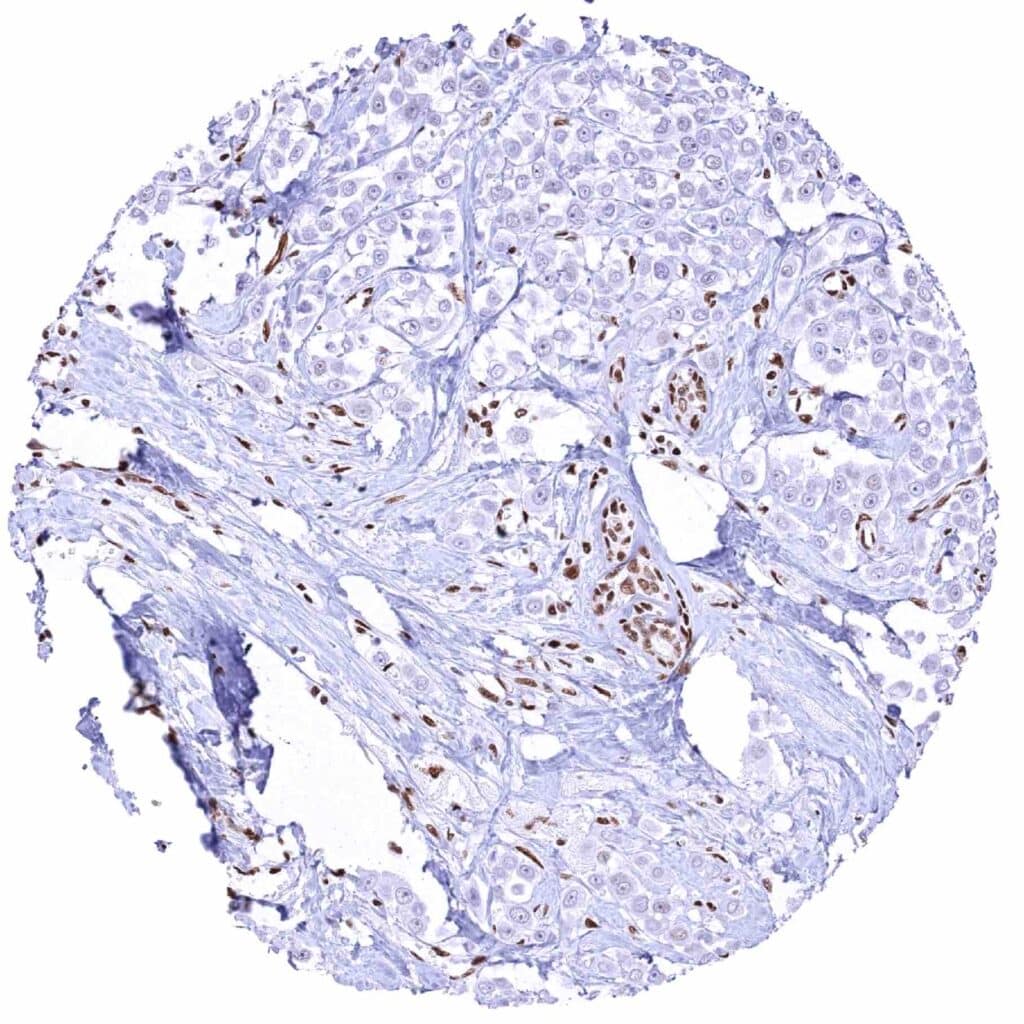

Prostate – GR negative adenocarcinoma (Gleason 4+4=8) with strong GR positivity of stromal cells